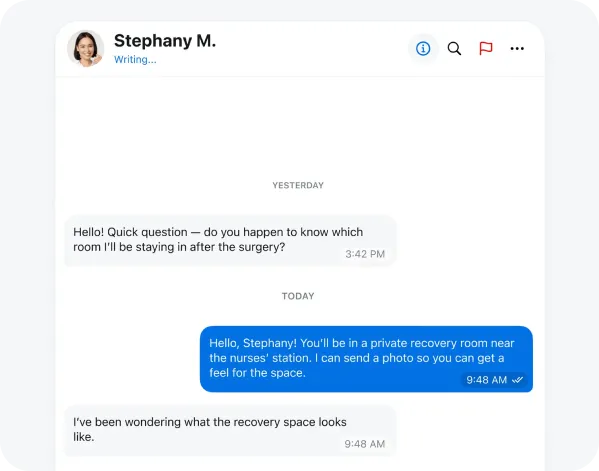

Discover Next-Gen Healthcare Management – Watch Live

Smarter Healthcare Solutions for Modern Patients

Virtual Healthcare Consultations Anytime, Anywhere

Intelligent Digital Assistant for Healthcare Needs